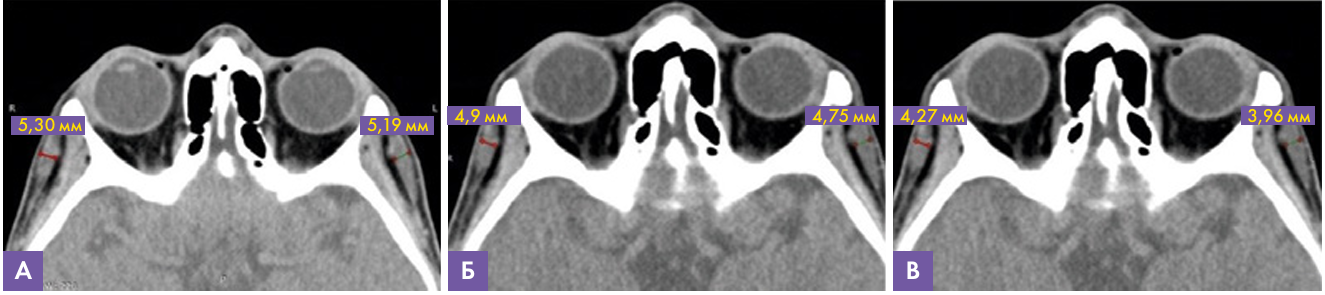

Данные МСКТ (рис. 4): на аксиальном срезе височной области в межфасциальном пространстве височной области при динамическом исследовании через 12 месяцев после введения имплантата на основе гиалуроновой кислоты определяется уменьшение его толщины с 5,4 мм до 4,27 справа и с 5,3 мм до 3,96 мм слева. Данных за наличие инфильтративных изменений, признаков миграции и инкапсулирования препарата не выявлено.

Рис. 4. МСКТ сканы височной области, аксиальная проекция.

А – через 5 месяцев, толщина имплантата слева 5.19 мм, справа 5.30 мм

В – через 9 месяцев, толщина имплантата слева 4,75 мм, справа 4,9 мм

С – через 12 месяцев, толщина имплантата слева 3,96 мм, справа 4,27 мм